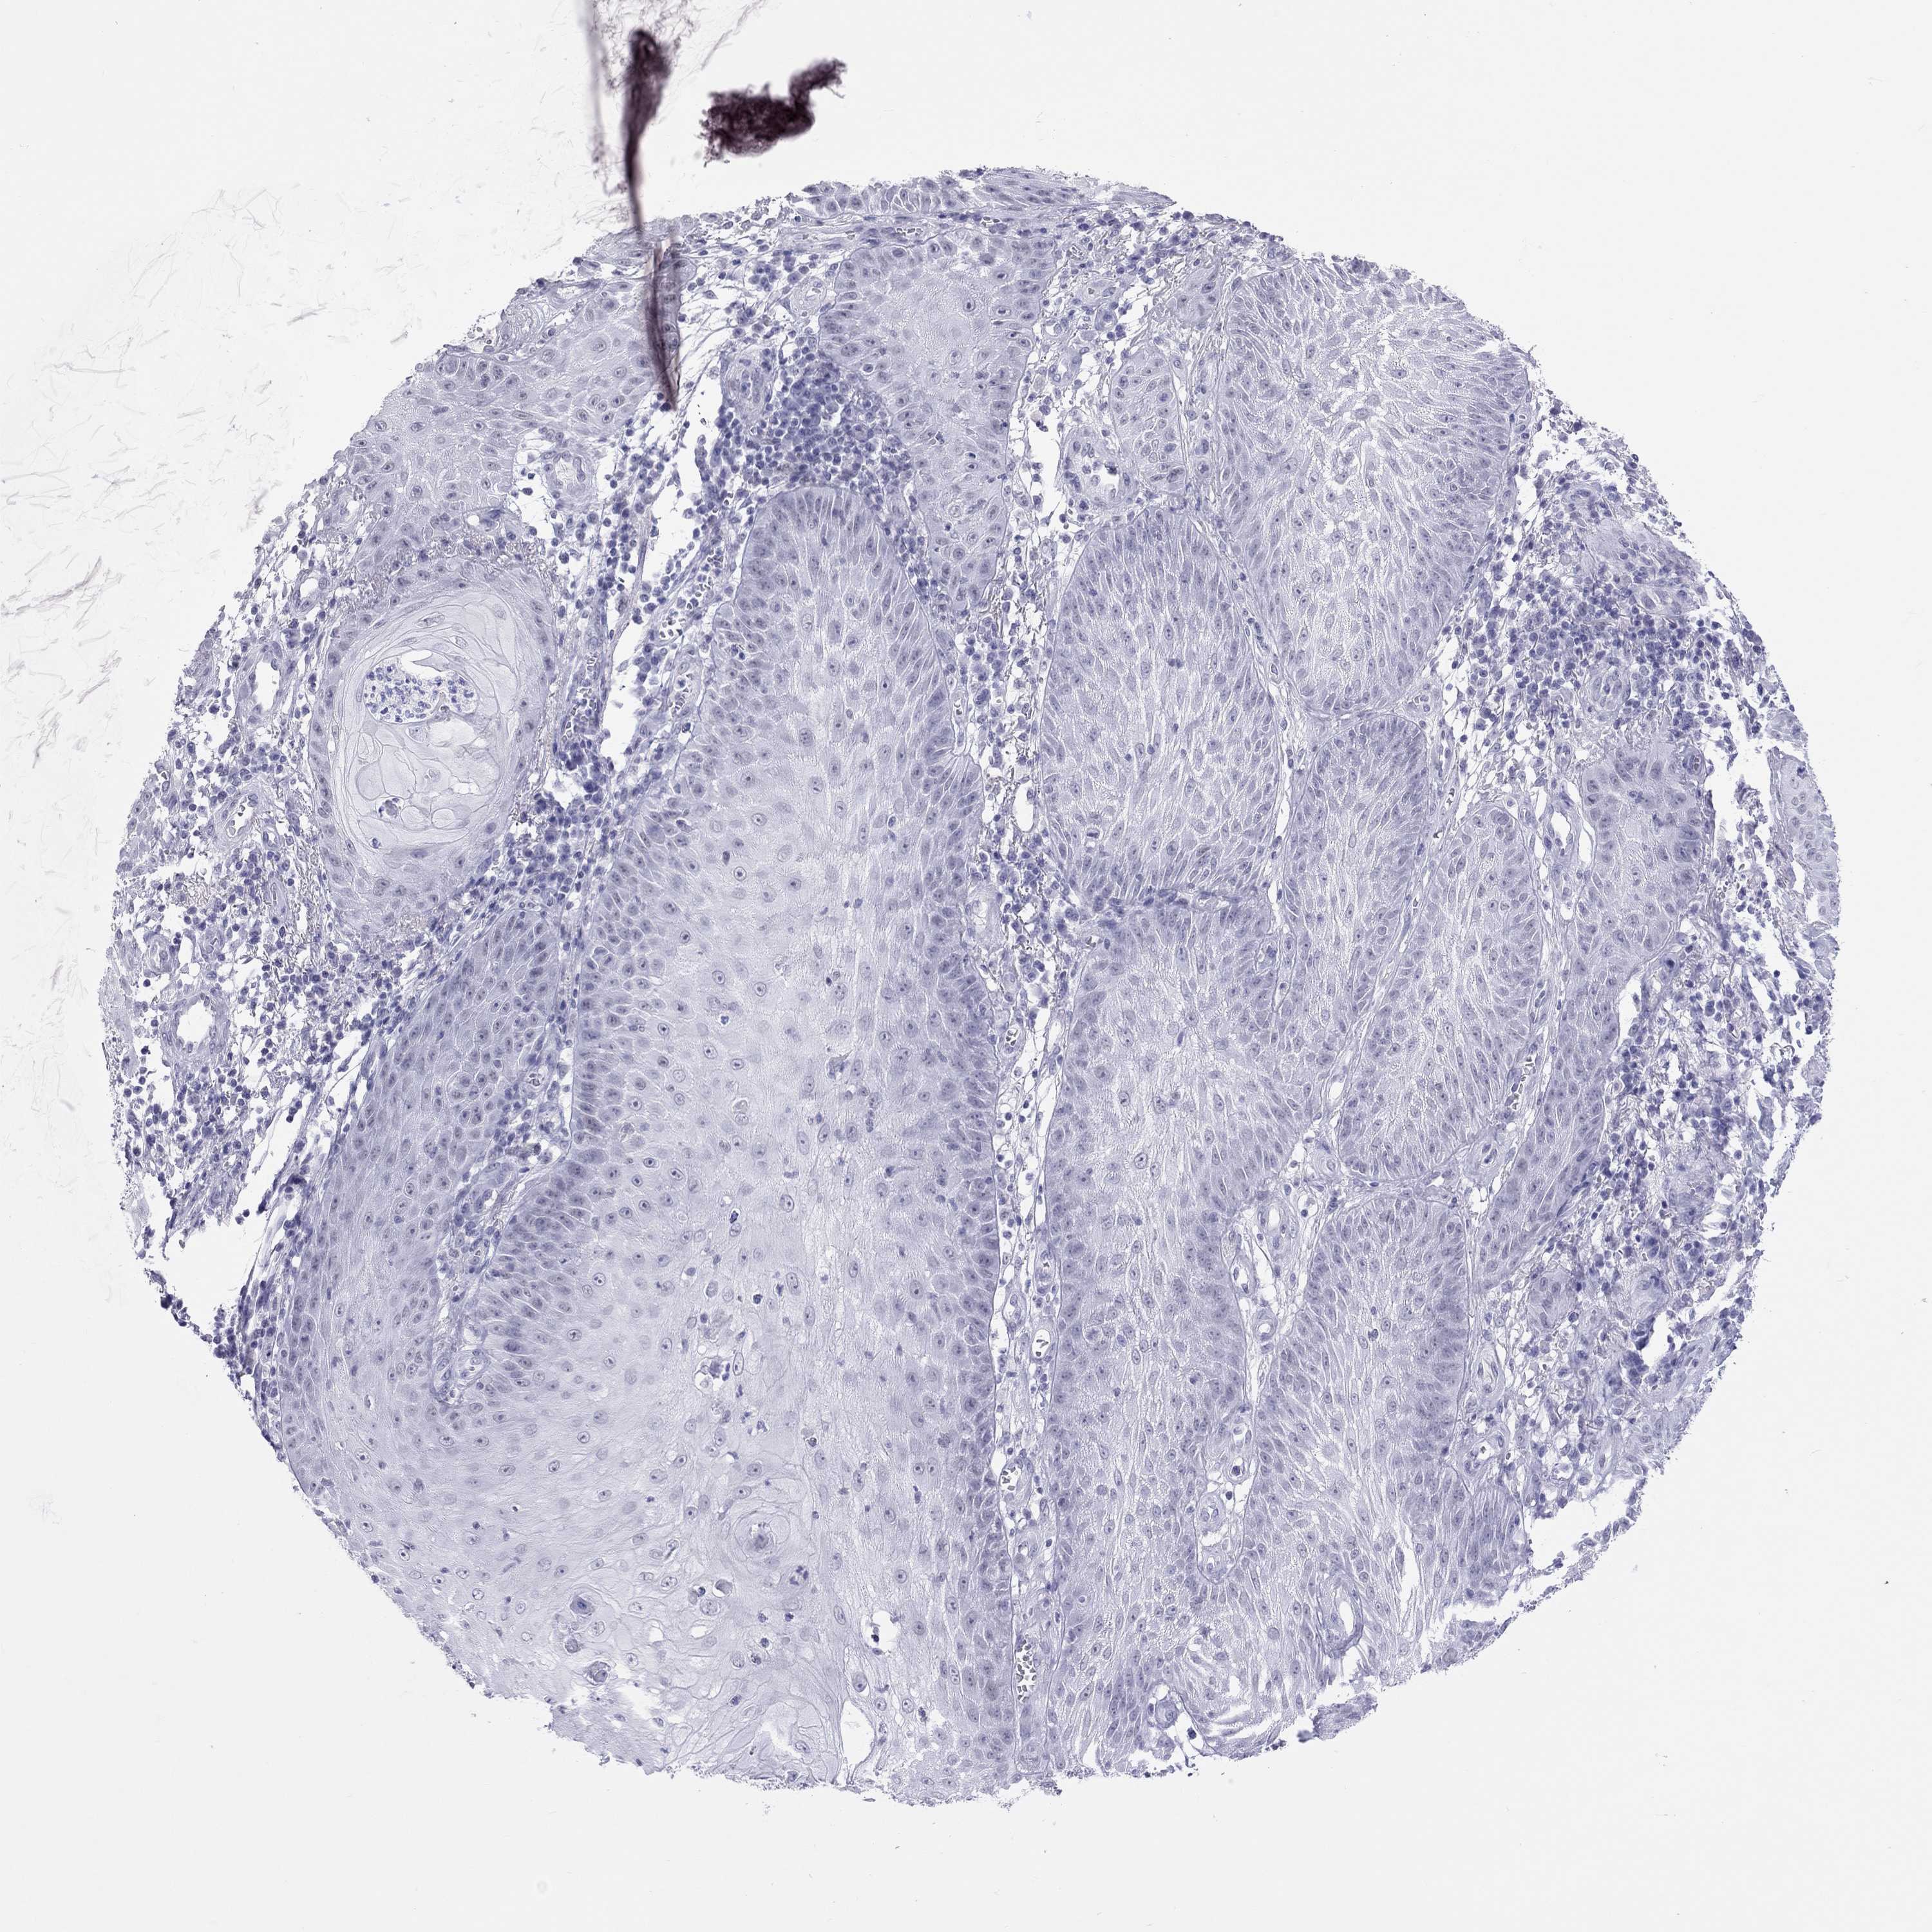

Basal cell and squamous cell cancer

SKIN CANCER - Protein expressioni

A mouse-over function shows sample information and annotation data. Click on an image to view it in a full screen mode. Samples can be filtered based on level of antibody staining by selecting one or several of the following categories: high, medium, low and not detected. The assay and annotation is described here.

Each image is clickable and will lead to virtual microscopy that enables deeper exploration of all samples and also displays staining intensity scores, fraction scores and subcellular localization as well as patient and tissue information for each sample.

Antibody HPA077658

Basal cell carcinoma

Squamous cell carcinoma, NOS